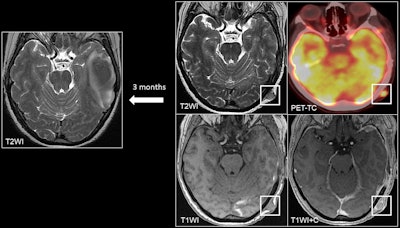

A 45-year-old patient with melanoma presented with a left temporal hemorrhagic metastasis. At the 3-month follow-up, a left occipital cutaneous/subcutaneous metastasis appeared as a soft tissue lesion with contrast enhancement on postcontrast T1 sequences and on PET/CT.All figures courtesy of Dr. Zhao Hui Chen Zhou et al and presented at ECR 2025.

Cutaneous and subcutaneous soft tissue metastases are rare, accounting for approximately 0.7% to 10% of cases, but usually indicate widespread metastatic disease and a poor prognosis. Primary sites vary according to gender, with the most common sites in women being breast, lung, gynecological, and gastrointestinal (in decreasing order), and in men being lung and gastrointestinal, they wrote.

These metastases may present as generally small nodules (< 2 cm) or infiltrative masses with homogeneous or heterogeneous enhancement. Imaging is not specific but must be considered in the context of a history of systemic cancer, and biopsy is mandatory in cases where there is no known primary tumor.